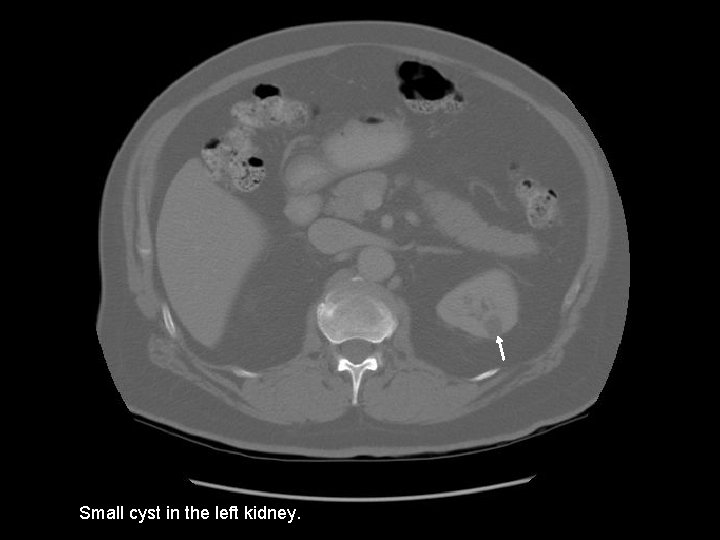

Small cyst in the left kidney.